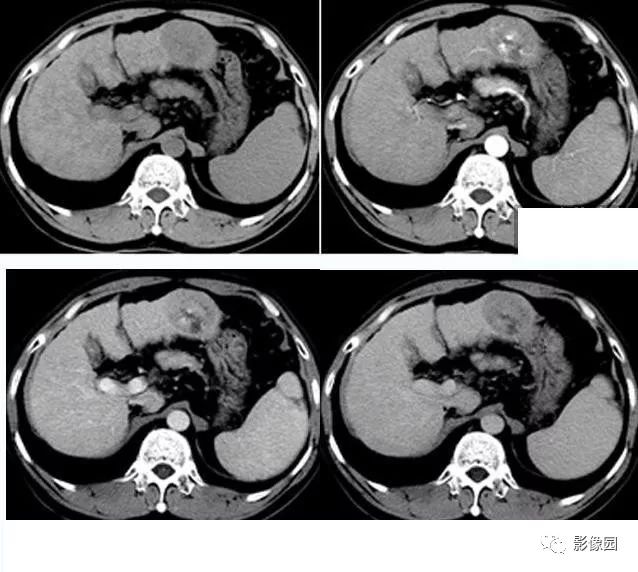

典型肝细胞肝癌ct表现 影像园 微信公众号文章阅读 Wemp